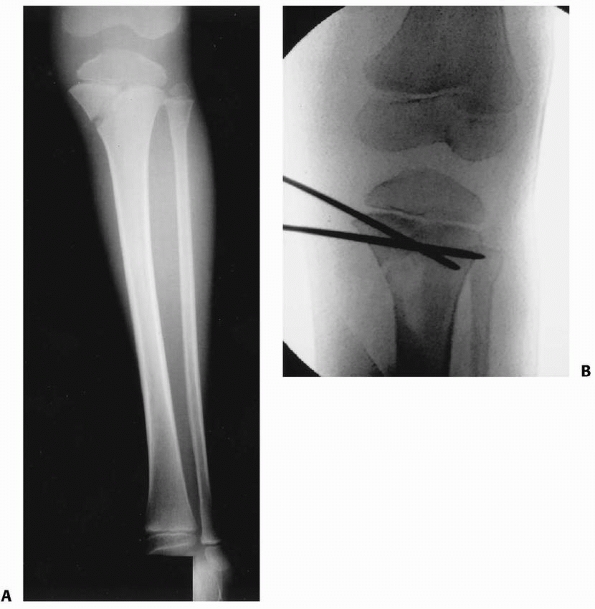

![]() |

|

FIGURE 25-9 A. Anteroposterior image of a Salter-Harris type II fracture of the proximal tibia. Notice the valgus alignment. B. This fracture was treated with percutaneous pin fixation after reduction. C. This patient developed tibia valga over a period of approximately 2 years following the injury. D. A medial proximal tibial hemiepiphysiodesis using a staple was performed.